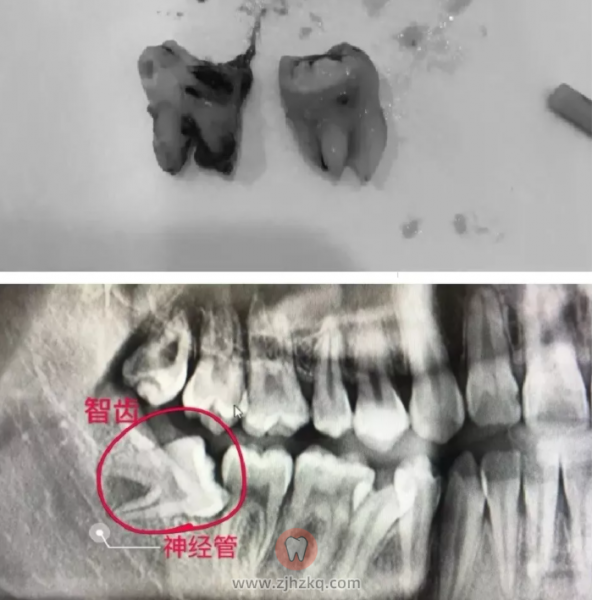

“不是每一个牙医都能做根管治疗”,施医生说,根管治疗是一个复杂繁琐的治疗过程,除了要求客户本身的配合,主诊医生还必须有足够的操作经验,再配合先进的技术设备,才能尽可能地延长牙齿本身的使用年限。可以说,“根管治疗”做的是否完善,直接决定这颗牙齿未来的使用寿命。